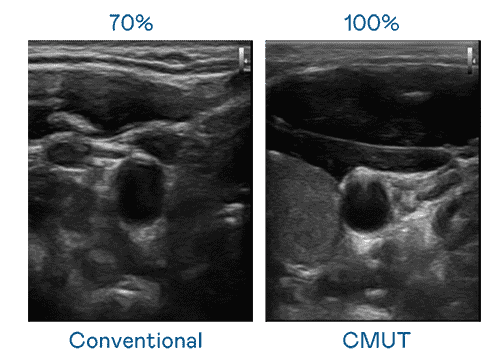

CMUT 技术是一种用电容式微机电元件来产生超音波讯号的技术。。与传统 PZT 压电式技术相比,,,,CMUT 频宽增加 30%,,,,更宽频的超音波讯号让影像解析度大幅提升,,,是实现高影像品质医疗超音波扫描、、、、促进精准医疗发展的关键技术。。

大频宽带来超清晰影像

超音波影像的解析度高低,,,,首先取决于探头能发出的讯号频宽。。。。欧陆注册 CMUT 可提供高清晰的超音波讯号,,提供高频宽、、、高灵敏度、、影像纹理细节更高的超音波影像,,,,协助医护人员缩短影像判读时间及利用精准的医疗影像进行诊断。。。。